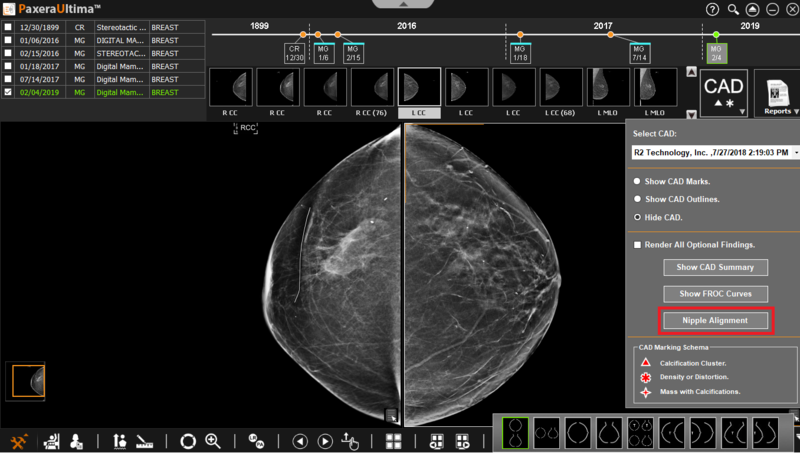

Click on the ‘CAD menu’ button and then on the ‘Nipple alignment’ button: